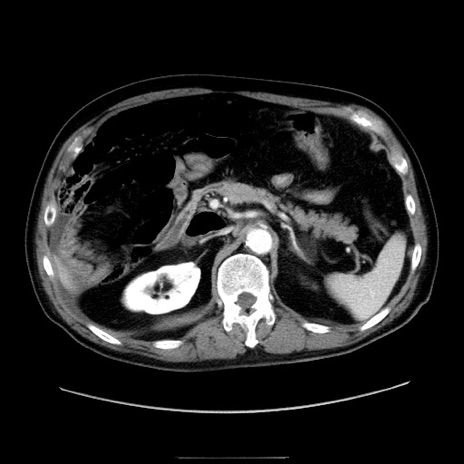

冠状断像

【症例】80歳代男性

【現病歴】約6時間前から臍下部痛が出現。次第に腹部膨隆・背部痛も生じてきたため来院。背部痛の場所は変化しない。

【身体所見】意識清明、BT 36.3℃、BP  131/87mmHg、P 87bpm、SpO2 100%(RA)、臍周囲自発痛・圧痛あり、反跳痛なし、自発痛部位に一致して板状硬あり、腹部膨隆、腸雑音減弱、CVA tenderness両側陰性。